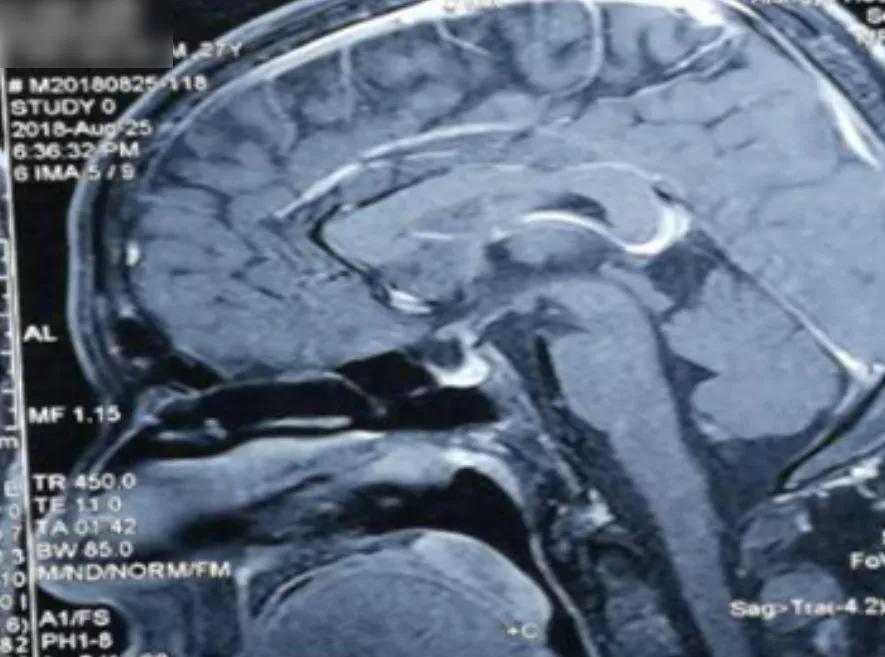

头部鞍区磁共振增强:垂体柄局部结节样增粗(图6)。

图6:鞍区磁共振

放射科: 临床及影像学表现符合结节病,Ⅰ期和Ⅱ期结节病可以有对称性肺门纵隔淋巴结肿大,Ⅲ期结节病肺内出现结节和纤维化病变,纵隔淋巴结消失,Ⅳ期结节病出现蜂窝肺,并且结节病非常容易累及颅内垂体,导致尿崩症,该患者完全符合。

内分泌科: 患者颅内垂体部位可以看到结节状增粗,临床表现为尿量明细增多,9000ml/24h,表现为尿崩症,禁水试验支持尿崩症诊断,虽然还有一些检查没有完善,但是结合头颅影像学特征,考虑垂体增粗受累,与肺内病变为同一种疾病导致,用一元论解释,考虑结节病。

呼吸科: 结节病为病因不明的系统性肉芽肿性疾病,任何器官均可以受累,结节病的诊断属于排他诊断,需要全面分析,排除可能引起肉芽肿的一系列疾病,如细菌、真菌、分枝杆菌、寄生虫感染、异物肉芽组织、过敏性非肺炎和肉芽肿性多血管炎也需要重点检查,需要注意的是能够引起垂体性尿崩症的非感染性疾病只有两个,一个是朗格罕细胞组织细胞增生症,另一个便是结节病。所以,根据患者特有的肺部和头颅影像学特征,结合病理学特点,最终可以做出正确的诊断。